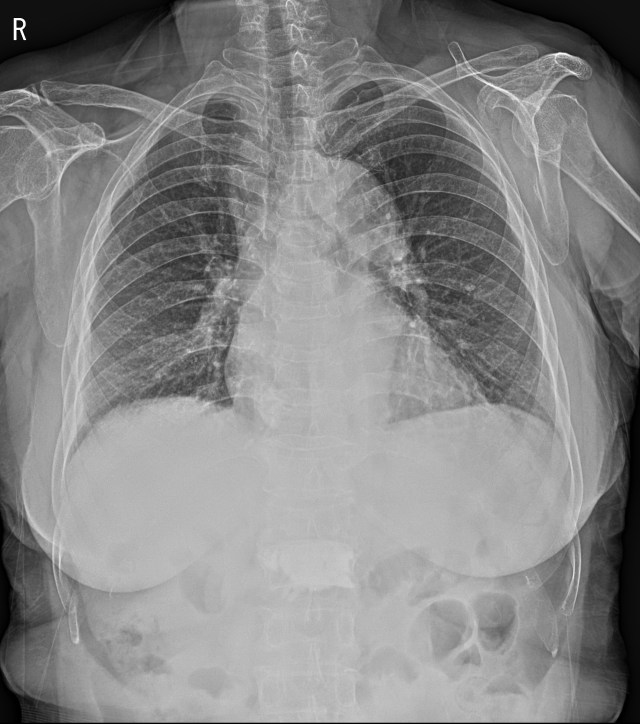

80세 할머니가 3일 전에 넘어지셨다고 합니다. 넘어진 후로 왼쪽 가슴이 아팠지만, 그냥 참고 있다가 통증이 점점 심해져서 내워하셨습니다. 흉부 x선 영상에서는 뚜렷한 이상소견은 보이지 않습니다.

넘어진 과거력에 왼쪽 가슴에 통증이 있기에 늑골 골절의 가능성을 의심해서 Rib series를 촬영했습니다. 꼼꼼히 봐도 아무런 골절의심소견이 보이지 않습니다.